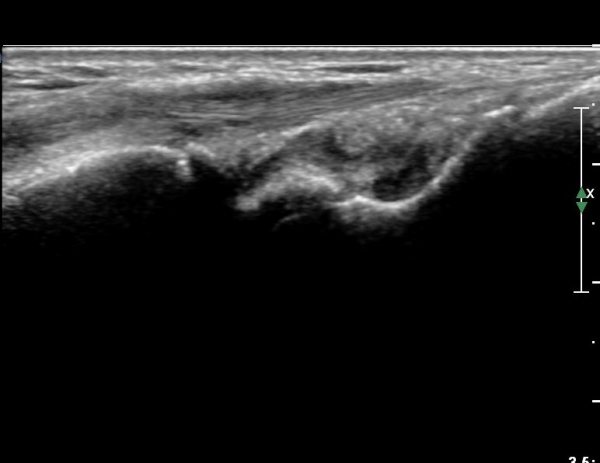

¼Õ¸ñÀÇ Á¾´Ü¸é°Ë»ç¿¡¼­ ¼Õ¸ñ °üÀý³» ºÎÁ¾ÀÌ °üÂûµÊ(»çÁø 1).

ŽÃÍÀÚ¸¦ ¾à°£ ôÃ÷À¸·Î À̵¿ÇÏ´Ï ¿ä°ñ ¸»´Ü¿¡ ÇÇÁú°ñ ¿¬°á¼º ¼Ò½Ç(loss of cotical continuity)ÀÌ °üÂûµÊ(»çÁø 2, 3).